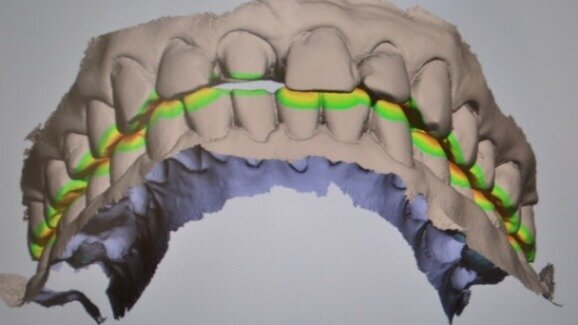

Kolejnym etapem jest zarejestrowanie okluzji. W tym celu prosimy pacjenta o zagryzienie zębów i skanujemy grupę 2-3 zębów dolnych wraz z przylegającym do nich dziąsłem oraz grupę 2-3 zębów przeciwstawnych(górnych), także z przylegającym dziąsłem.Skaner automatycznie składa zeskanowane wcześniej łuki górny i dolny w prawidłowym okluzyjnym położeniu (Ryc. 6).

Jeszcze jedna ważna cecha skanera wewnątrzustnego ułatwiająca bezpośrednią diagnostykę to analiza odległości łuków zębowych względem siebie, a szczególnie odległości oszlifowanego zęba od zęba przeciwstawnego. Do określenia tych wartości służy skalibrowana mapa kolorów (Ryc. 24-26).